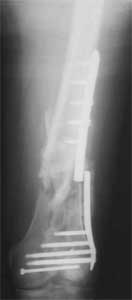

KEMMD> method of treatment for distal femur fractures

A new toy is more interesting and fashionable. And anyway it is not panacea, i have already seen presentations with LISS failures like the attached one presented by D.Seligson. And people also demonstrated incisions say that the method is not so LESS invasive as it supposed to be.